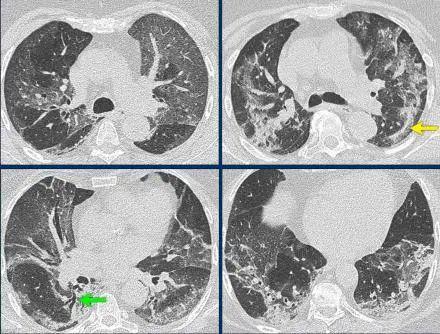

当孩子出现发热伴有咳嗽、气促、或者呼吸费力,这种情况就是提示患儿可能患有肺炎,需要让大夫听诊肺部,如果听到固定性中、细湿啰音,此时临床可确诊肺炎。如果上述表现不明显,可进一步完善胸部影像学检查,例如胸片、胸部CT,有斑、片状阴影同样可确诊。